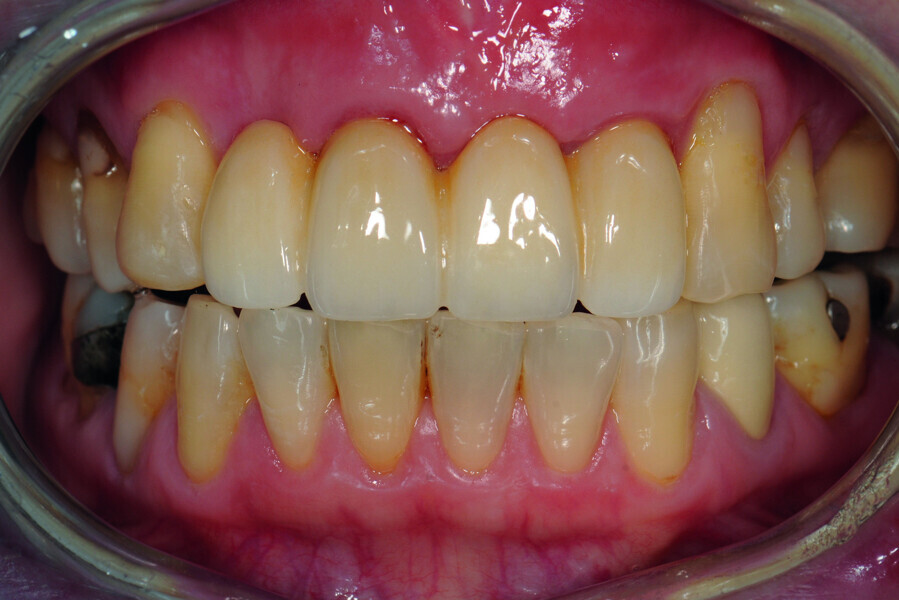

Fig. 43: Frontal view of the anterior teeth just after delivery.

Fig. 44: ICP occlusal contact (12 μm occluding paper, red).